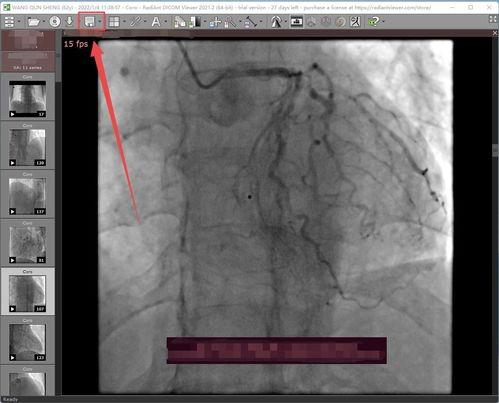

首先,得先弄清楚什么是心脏造影。心脏造影是一种医学检查方法,通过注入造影剂,使心脏的血管在X射线下显影,从而观察心脏的结构和功能。而真人心脏造影,顾名思义,就是用真实的人体心脏进行造影,记录下心脏跳动的全过程。

这段真人心脏造影视频,让我看到了一个跳动不止的生命。视频中,心脏的肌肉在不断地收缩和舒张,仿佛在诉说着生命的顽强。你可以清晰地看到心脏的四个腔室,以及它们之间的血管连接。每一个细节都如此真实,让人不禁为之心动。

你知道吗?这段视频之所以如此清晰,得益于现代医学技术的突破。现在的真人心脏造影技术已经非常成熟,可以捕捉到心脏跳动的每一个瞬间。而且,视频的分辨率极高,让人仿佛置身于现场,亲眼目睹心脏的跳动。

真人心脏造影视频不仅具有观赏价值,更重要的是,它具有极高的医学价值。医生可以通过这段视频,更直观地了解患者的心脏状况,从而为诊断和治疗提供有力依据。对于那些患有心脏疾病的人来说,这样的视频无疑是一种福音。